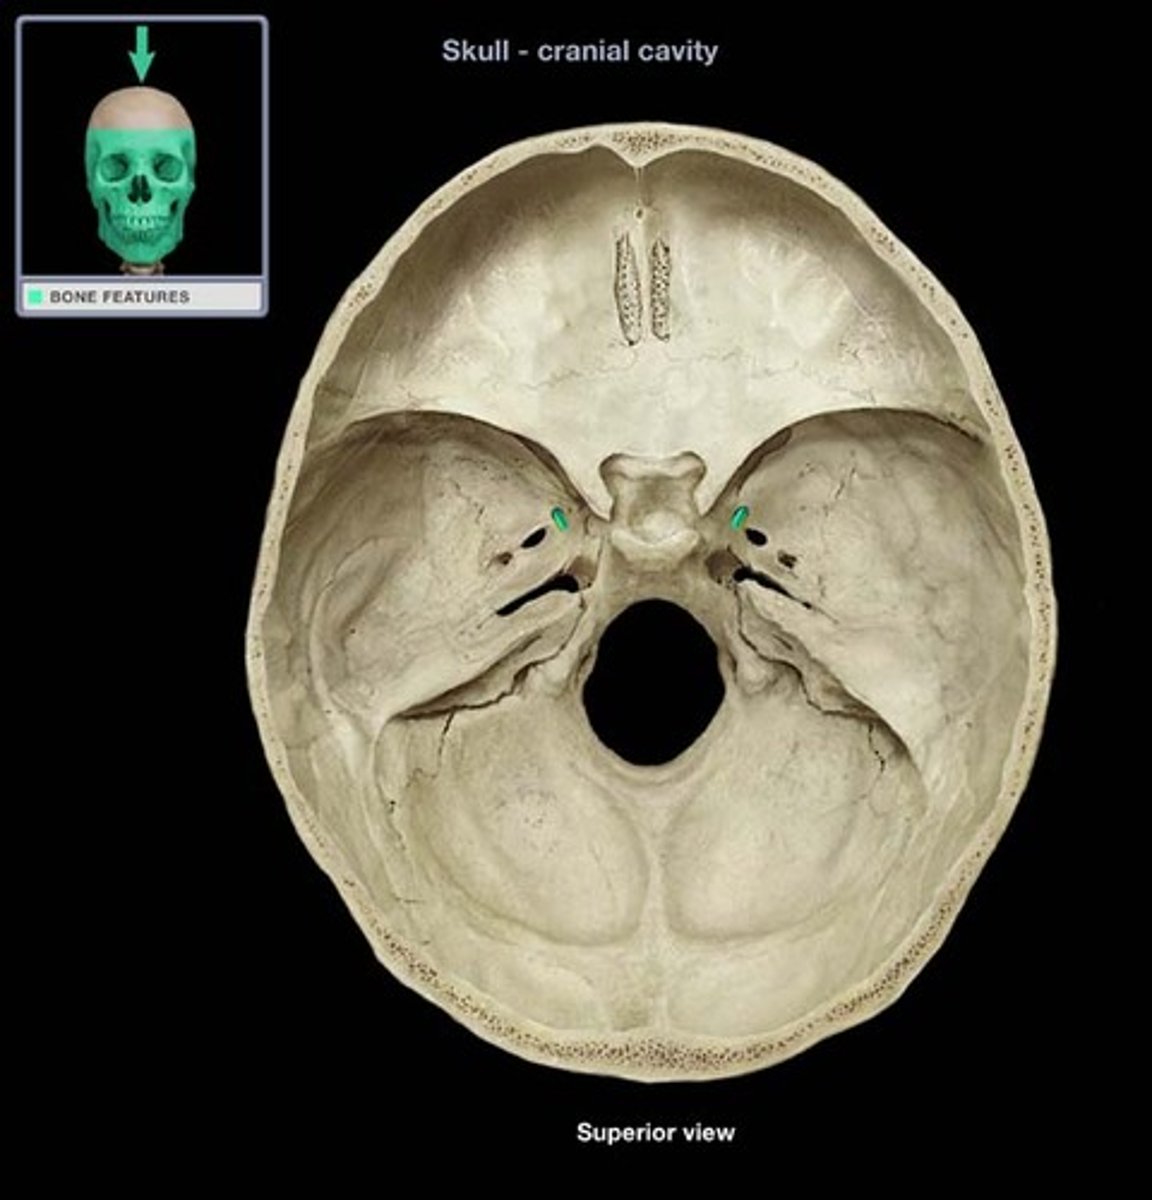

optic canal

hole that transmits the optic nerve (CN II) & the opthalmic artery

superior orbital fissure

opening that transmits cranial nerves III, IV, V1 and VI, and the superior opthalmic vein